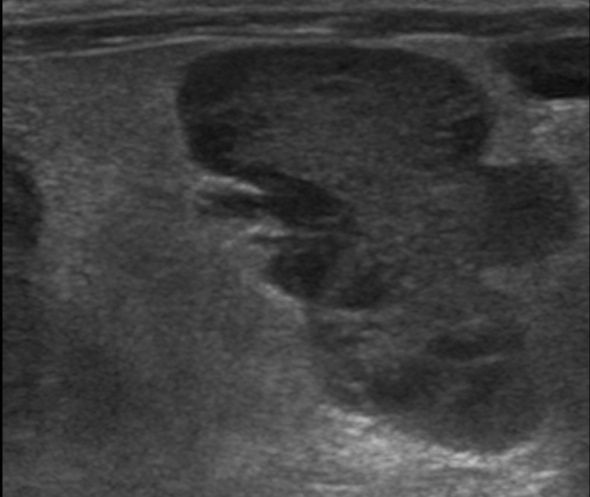

Lorsque les glandes surrénales sont fortement stimulées, elles deviennent progressivement hyperplasiques puis tumorales (tumeur bénigne puis maligne). Le diagnostic peut être établi par échographie, réalisée par un vétérinaire expérimenté avec les furets, et par une prise de sang (dosage des hormones en question). Suivant l'extension et la présence ou non d'embole vasculaire, il est recommandé de poser un implant hormonal ou de réaliser une surrénalectomie. Cette chirurgie est particulièrement risquée à cause de la proximité des glandes surrénales avec l'aorte, un vaisseau sanguin vital pour l'organisme. Il peut être utile d'utiliser des outils de microchirurgie ainsi que du matériel de pointe tel qu'une caméra endoscopique per-opératoire Vitum pour maximiser la réussite de la chirurgie.

Le diagnostic se fait par prise de sang et par échographie, réalisée par un vétérinaire expérimenté. Parfois, un traitement doit être administré en urgence, car les crises d'hypoglycémie peuvent être mortelles. Une hospitalisation est nécessaire en cas de crises convulsives. Les premières phases du traitement sont médicales mais une chirurgie (pancréatectomie) peut être recommandée dans certaines formes d'insulinome. Nous utilisons pour ce faire la technologie Ligasure pour minimiser le temps opératoire et les risques associés à l'opération.